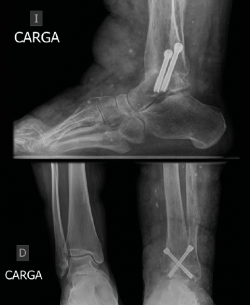

El procedimiento se realizó con el paciente en la posición prona y el uso de 2 portales posteriores. Las superficies articulares se desbridaron retirando el cartílago por medios artroscópicos y la articulación se fijó con 2 tornillos cruzados. La fusión se logró completamente a los 6 meses de seguimiento. A los 2 años de seguimiento, el paciente es capaz de mantener la bipedestación prolongada y caminar largas distancias sin dolor.

The procedure was performed with the patient in the prone position and the use of 2 posterior portals. The articular surfaces were debrided by removing the cartilage by arthroscopic means, and the joint was fixed with 2 crossed screws. Fusion was completely achieved at 6 months follow-up. At 2-year follow-up, patient is pain free and able to walk long distances.

La paciente se mantuvo en descarga total durante un mes, comenzando la carga parcial durante 2 meses más con una bota de tipo CAM (controlled ankle motion) Walker. Se realizaron controles radiográficos intraoperatorios, a las 6 semanas, 3 y 6 meses, y 1 año. El seguimiento clínico se prolongó hasta los 2 años tras el procedimiento.

A los 6 meses se obtuvieron signos radiográficos de consolidación completa de la artrodesis (Figura 5). La paciente refirió una resolución completa del dolor y mejoría de la capacidad para la deambulación a los 6 meses, que se mantuvo en los siguientes controles.